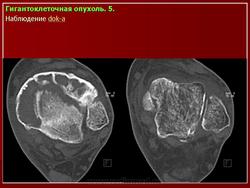

Рентгенологическое исследование гигантоклеточной опухоли показывает, что гигантоклеточиая опухоль локализуется в эпифизе и распространяется на метаэпифизарную часть кости. Поражение носит литический характер, имеет четкие контуры и умеренно или слабо контрастные костные балки. На границе метафиза контуры новообразования менее четкие, чем на остальном протяжении. Склеротические изменения вокруг опухоли развиваются редко, а такие угрожающие признаки, как козырек Кодмена или «лучистый венец», очень редки. Многие гигантоклеточные опухоли не выходят за пределы пораженной кости, но иногда они прорастают кортикальный слой и выходят в мягкие ткани, где покрываются тонким слоем новообразованной кости, едва заметкой при рентгенологическом исследовании. Такие же новообразования кости в виде «яичной скорлупы» имеются в имплантатах опухоли в мягких тканях и в метастазах в легких. Некоторые исследователи различают три стадии развития гигантоклеточной опухоли. На первой стадии узел небольшой, бессимптомный и не выходит за пределы пораженной кости. Вторая стадия документируется довольно объемным новообразованием, вплотную подходящим к наружному контуру кости. На третьей стадии опухоль проявляет агрессивные свойства и дает яркую клиническую симптоматику, связанную с се быстрым ростом и возникновением патологического перелома. На компьютерной томограмме отмечаются деструкция кортикального и медуллярного слоев и проникновение опухоли в окружающие мягкие ткани.